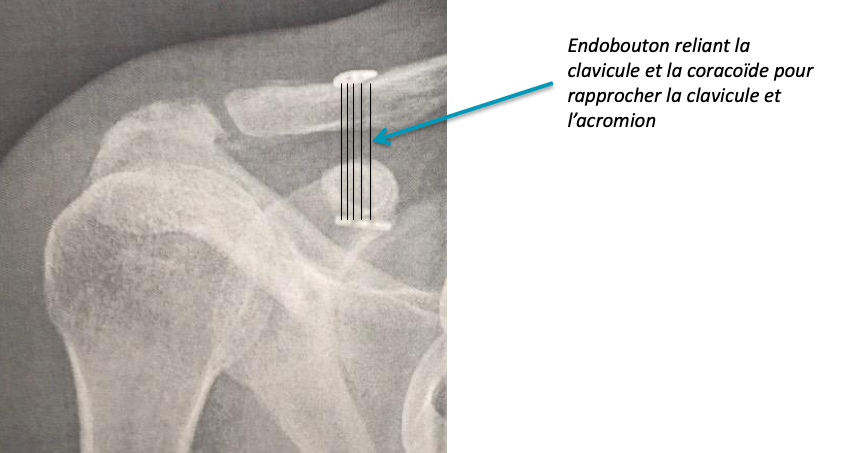

Diverses méthodes chirurgicales ont été utilisées pour stabiliser l’articulation acromio-claviculaire luxée. Actuellement, la méthode la plus souvent réalisée est une technique sous arthroscopie qui consiste à rapprocher la clavicule de la coracoïde en utilisant des matériaux synthétiques (endoboutons). Ces endoboutons permettent de guider la cicatrisation des ligament coraco-claviculaires. L’opération est réalisée sous anesthésie générale en ambulatoire (vous entrez et sortez le même jour que votre intervention).

Diverses méthodes chirurgicales ont été utilisées pour stabiliser l’articulation acromio-claviculaire luxée. Actuellement, la méthode la plus souvent réalisée est une technique sous arthroscopie qui consiste à rapprocher la clavicule de la coracoïde en utilisant des matériaux synthétiques (endoboutons). Ces endoboutons permettent de guider la cicatrisation des ligament coraco-claviculaires. L’opération est réalisée sous anesthésie générale en ambulatoire (vous entrez et sortez le même jour que votre intervention).